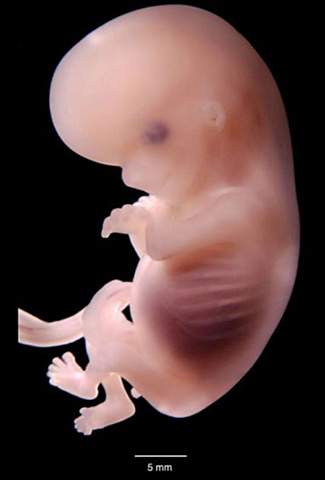

• Semana 8

Semana 8

El embrión mide aproximadamente 13 mm desde la punta de la cabeza hasta las nalgas.Comienza en su cabeza a formarse y perfilarse las orejas , los ojos y donde empieza a formarse la punta de la nariz, la cabeza es todavía muy grande en comparación con el resto del cuerpo. Por eso, aunque su columna vaya enderezándose poco a poco, la cabeza todavía permanece hacia delante. También comienza a borrarse la columna del embrión y comienza a formarse los cuatro huesos unidos los cuales forman el coxis.